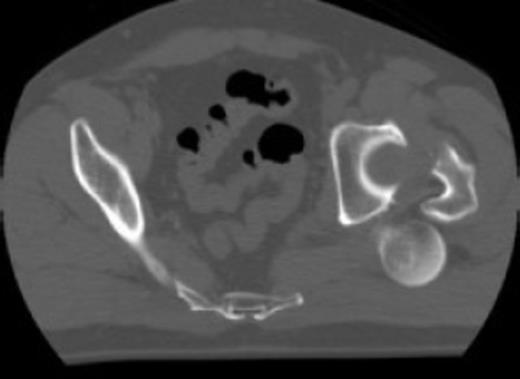

Posterior dislocation of the femoral head with no associated acetabular fracture

Antero-posterior radiograph of the pelvis confirmed a displaced transcervical femoral neck fracture with associated dislocation of the femoral head. Computed-tomography, confirmed a posterior dislocation of the femoral head with no associated acetabular fracture (Fig. 1,2,3).